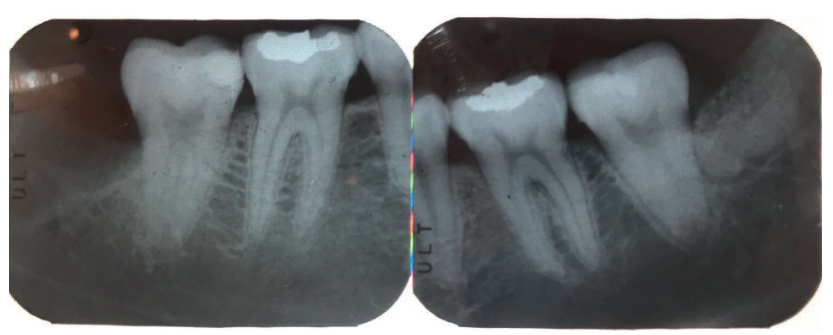

En la exploración radiográfica mediante radiografía panorámica se apreciaron ambos terceros molares inferiores retenidos, en una posición horizontal el 3.8 y mesioangular el 4.8 (Figura 1).

Tras obtener el consentimiento informado, se realizó un bloqueo anestésico mediante Articaína al 4% con adrenalina 1:100.000 del nervio dentario inferior y lingual, y posteriormente el nervio bucal. Se realizó una incisión festoneada lineal desde la cara distal del primer molar inferior izquierdo, hasta la cara distal del segundo molar inferior izquierdo, y se realizó una incisión oblicua hacia la rama ascendente mandibular. Tras el despegamiento mucoperióstico, se realizó una protección del nervio lingual durante las maniobras de ostectomía. Posteriormente se realizó la ostectomía necesaria para liberar el límite amelocementario del tercer molar inferior, procediendo a su luxación mediante botador recto, odontosección coronal con pieza de mano y fresa redonda de carburo de tungsteno, y exodoncia del fragmento radicular una vez retirado el fragmento coronal (Figura 2). El alveolo se lavó con suero fisiológico y se le hizo al paciente morder una gasa estéril empapada en clorhexidina al 0,12%, durante la preparación del material de injerto.